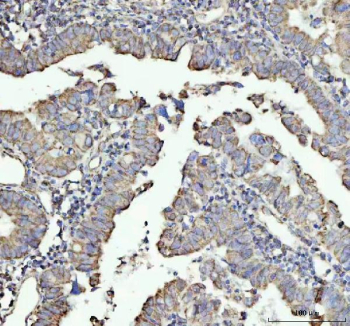

Immunohistochemical staining of NDUFAB1 using anti-NDUFAB1 antibody. NDUFAB1 was detected in a paraffin-embedded section of human colorectal adenocarcinoma tissue. Heat mediated antigen retrieval was performed in EDTA buffer (pH 8.0, epitope retrieval solution). The tissue section was blocked with 10% goat serum. The tissue section was then incubated with 1:50 rabbit anti-NDUFAB1 antibody overnight at 4oC. Peroxidase Conjugated Goat Anti-rabbit IgG was used as secondary antibody and incubated for 30 minutes at 37oC. The tissue section was developed using an HRP secondary and DAB substrate.